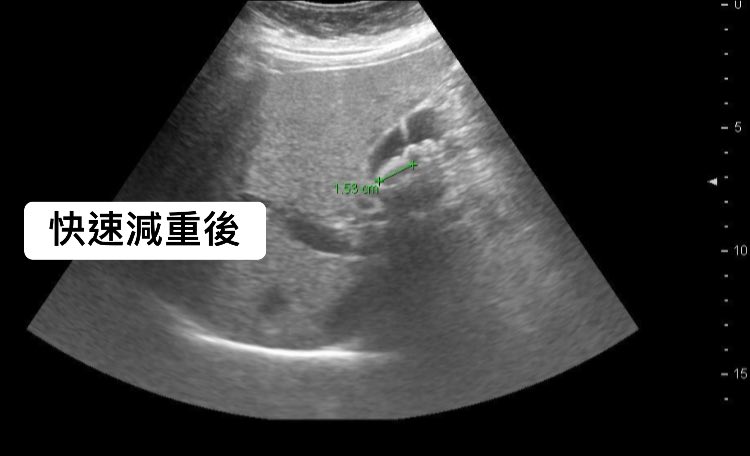

醫師進一步表示,過去曾遇到破百公斤的50歲脂肪肝病人,他在短時間內狂瘦20公斤,雖然減肥成功,卻在定期半年回診的腹部超音波中發現異常,膽結石不僅變多還變大!

圖/翻攝自 謝文斌醫師 肝膽腸胃專門 臉書